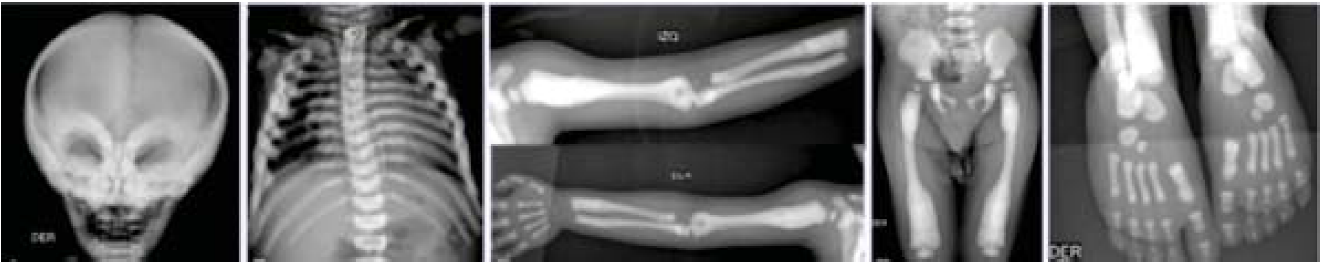

Seis meses después es hospitalizada por una segunda neumonía de origen bacteriano, además se detectó hipocalcemia de 2.5 mg/dL, por lo que la paciente requirió bolos de gluconato de calcio y calcitriol. Durante su revaloración se documentó atrofia óptica bilateral, ceguera, hipoacusia bilateral y hepatoesplenomegalia, todos hallazgos sugestivos de osteopetrosis. Con las radiografías se confirmó el diagnóstico, esclerosis difusa generalizada e imágenes de “hueso en hueso” característicos de esta enfermedad (Figura 1).

Figura 1 Con las radiografías de diferentes huesos se observa la osteoesclerosis característica de la osteopetrosis maligna infantil.

Niño de 5 años 7 meses, originario de Chiapas, con antecedente de una hermana que murió a los 6 meses de edad sin causa determinada, pero los padres refirieron que tuvo el mismo cuadro clínico. Fue enviado con el diagnóstico de osteopetrosis a los 11 meses al Instituto Nacional de Pediatría. A su ingreso se documentó peso de 6950 g (percentil -3) y talla de 65 cm (percentil -3), dismorfias faciales, fontanela anterior amplia, endotropía de ojo izquierdo, implantación baja de pabellones auriculares, puente nasal deprimido, micrognatia, pectus excavatum, cardiomegalia, hepatomegalia (4 cm debajo del borde costal), hipotonía severa y retraso psicomotor. Sus laboratorios mostraron anemia de 6.4 g/dL, trombocitopenia de 13 000/mm3 e hipocalcemia de 3.2 mg/dL. Se transfundieron plaquetas y paquete globular, además de administrar suplementos de calcio. Se documentaron las siguientes alteraciones radiográficas con las que se confirmó el diagnóstico de osteopetrosis: osteoesclerosis en base de cráneo, región periorbitaria, columna vertebral (vértebras en sándwich), metáfisis de fémur y huesos iliacos (figura 1). Durante su evolución cursó con múltiples neumonías tanto bacterianas como virales. Otra complicación fue hipertensión arterial pulmonar y cardiomegalia asociadas con tórax restrictivo. Con la misma metodología empleada en el caso 1 se determinó una mutación heterocigota compuesta en el gen TCIRG1 (OMIN *604592). La primera (encontrada en estado heterocigoto en la madre) fue una inserción de un solo nucleótido que predice un corrimiento del marco de lectura en la secuencia de aminoácidos (p.Gly159Argfs*68; NM_006019.3:c.474dup). La segunda (encontrada en estado heterocigoto en el padre) fue una duplicación de 29 nucleótidos en el exón 12, que predice corrimiento del marco de lectura en la secuencia de aminoácidos y codón de paro prematuro 79 aminoácidos río abajo (p.Phe459Leufs*79; NM_006019.3:c.1348_1376dup). La detección de las dos mutaciones en los dos alelos es compatible con el cuadro clínico de osteopetrosis, sumada al antecedente de una hermana menor con la misma sintomatología.

Los hallazgos radiológicos característicos incluyen marcado aumento en la densidad ósea con remodelación metafisiaria y apariencia de "hueso dentro de un hueso" (hueso menos denso sobre hueso más denso). La esclerosis focal de la base de cráneo y pelvis pueden presentar alternancia de bandas escleróticas, llamadas de “Lucent”, y placas en las vértebras (vértebras "sándwich"), típicas de formas adultas menos graves. La tomografía computarizada se puede utilizar para evaluar la vía óptica y el conducto auditivo, así como la efectividad del tratamiento. Otros datos clínicos son hipotrofia, mal estado general y atresia de coanas.1,3,10